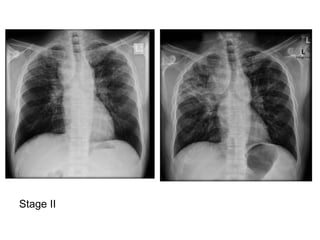

Stage 0 : normal chest radiograph

Stage II : nodal enlargement and parenchymal

disease

Stage II